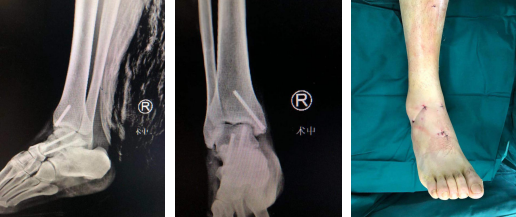

术后X线(左/中图),术后外观:创口很小(右图)

病例二:患者高师傅,42岁,一周前从2米高处摔落导致右距骨骨折、右内踝、后踝骨折,右跟骨骨折,同时还查有右外踝陈旧性骨折,右足马蹄内翻畸形。

术前影像

距骨骨折进行手术治疗有一个比较棘手的并发症,就是骨折不愈合和距骨缺血性坏死,治疗中精准的复位固定和尽可能地减少对距骨血供的伤害是关键。讨论后,石荣剑副院长曹广超主任团队决定利用踝关节镜联合机器人治疗距骨骨折。术中,进行关节镜下探查清理,克氏针撬拨复位骨折端;打入克氏针固定骨折端,再在机器人的精准辅助下打入导针,拧入螺钉。手术仅数个0.5厘米切口,创口微乎其微,患者非常满意。

术后(左/中图)创口微乎其微,患者非常满意(右图)